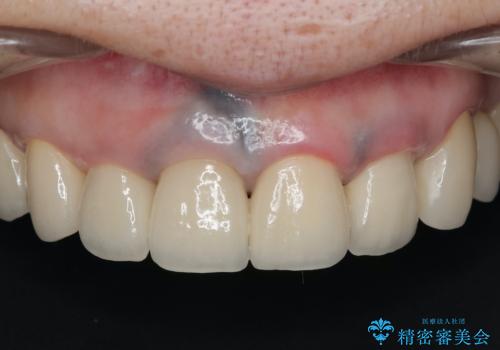

保険適応 硬質レジン前装冠から審美的でオールセラミッククラウンへ

- 変色の進んでしまった前歯を審美的なセラミック治療にしたい、と希望され来院されました。

10数年前に治療を行った保険適応の硬質レジン前装冠は変色劣化が進み、審美的に問題があるだけでなく虫歯のリスクも高くなり好ましくない状況です。

審美的かつ精度の高いセラミック治療を行うことで、汚れがつきにくく虫歯や歯周病の感染リスクを将来にわたって抑える治療が可能になります。

見違えるような審美的な仕上がりに満足いただくことができました。